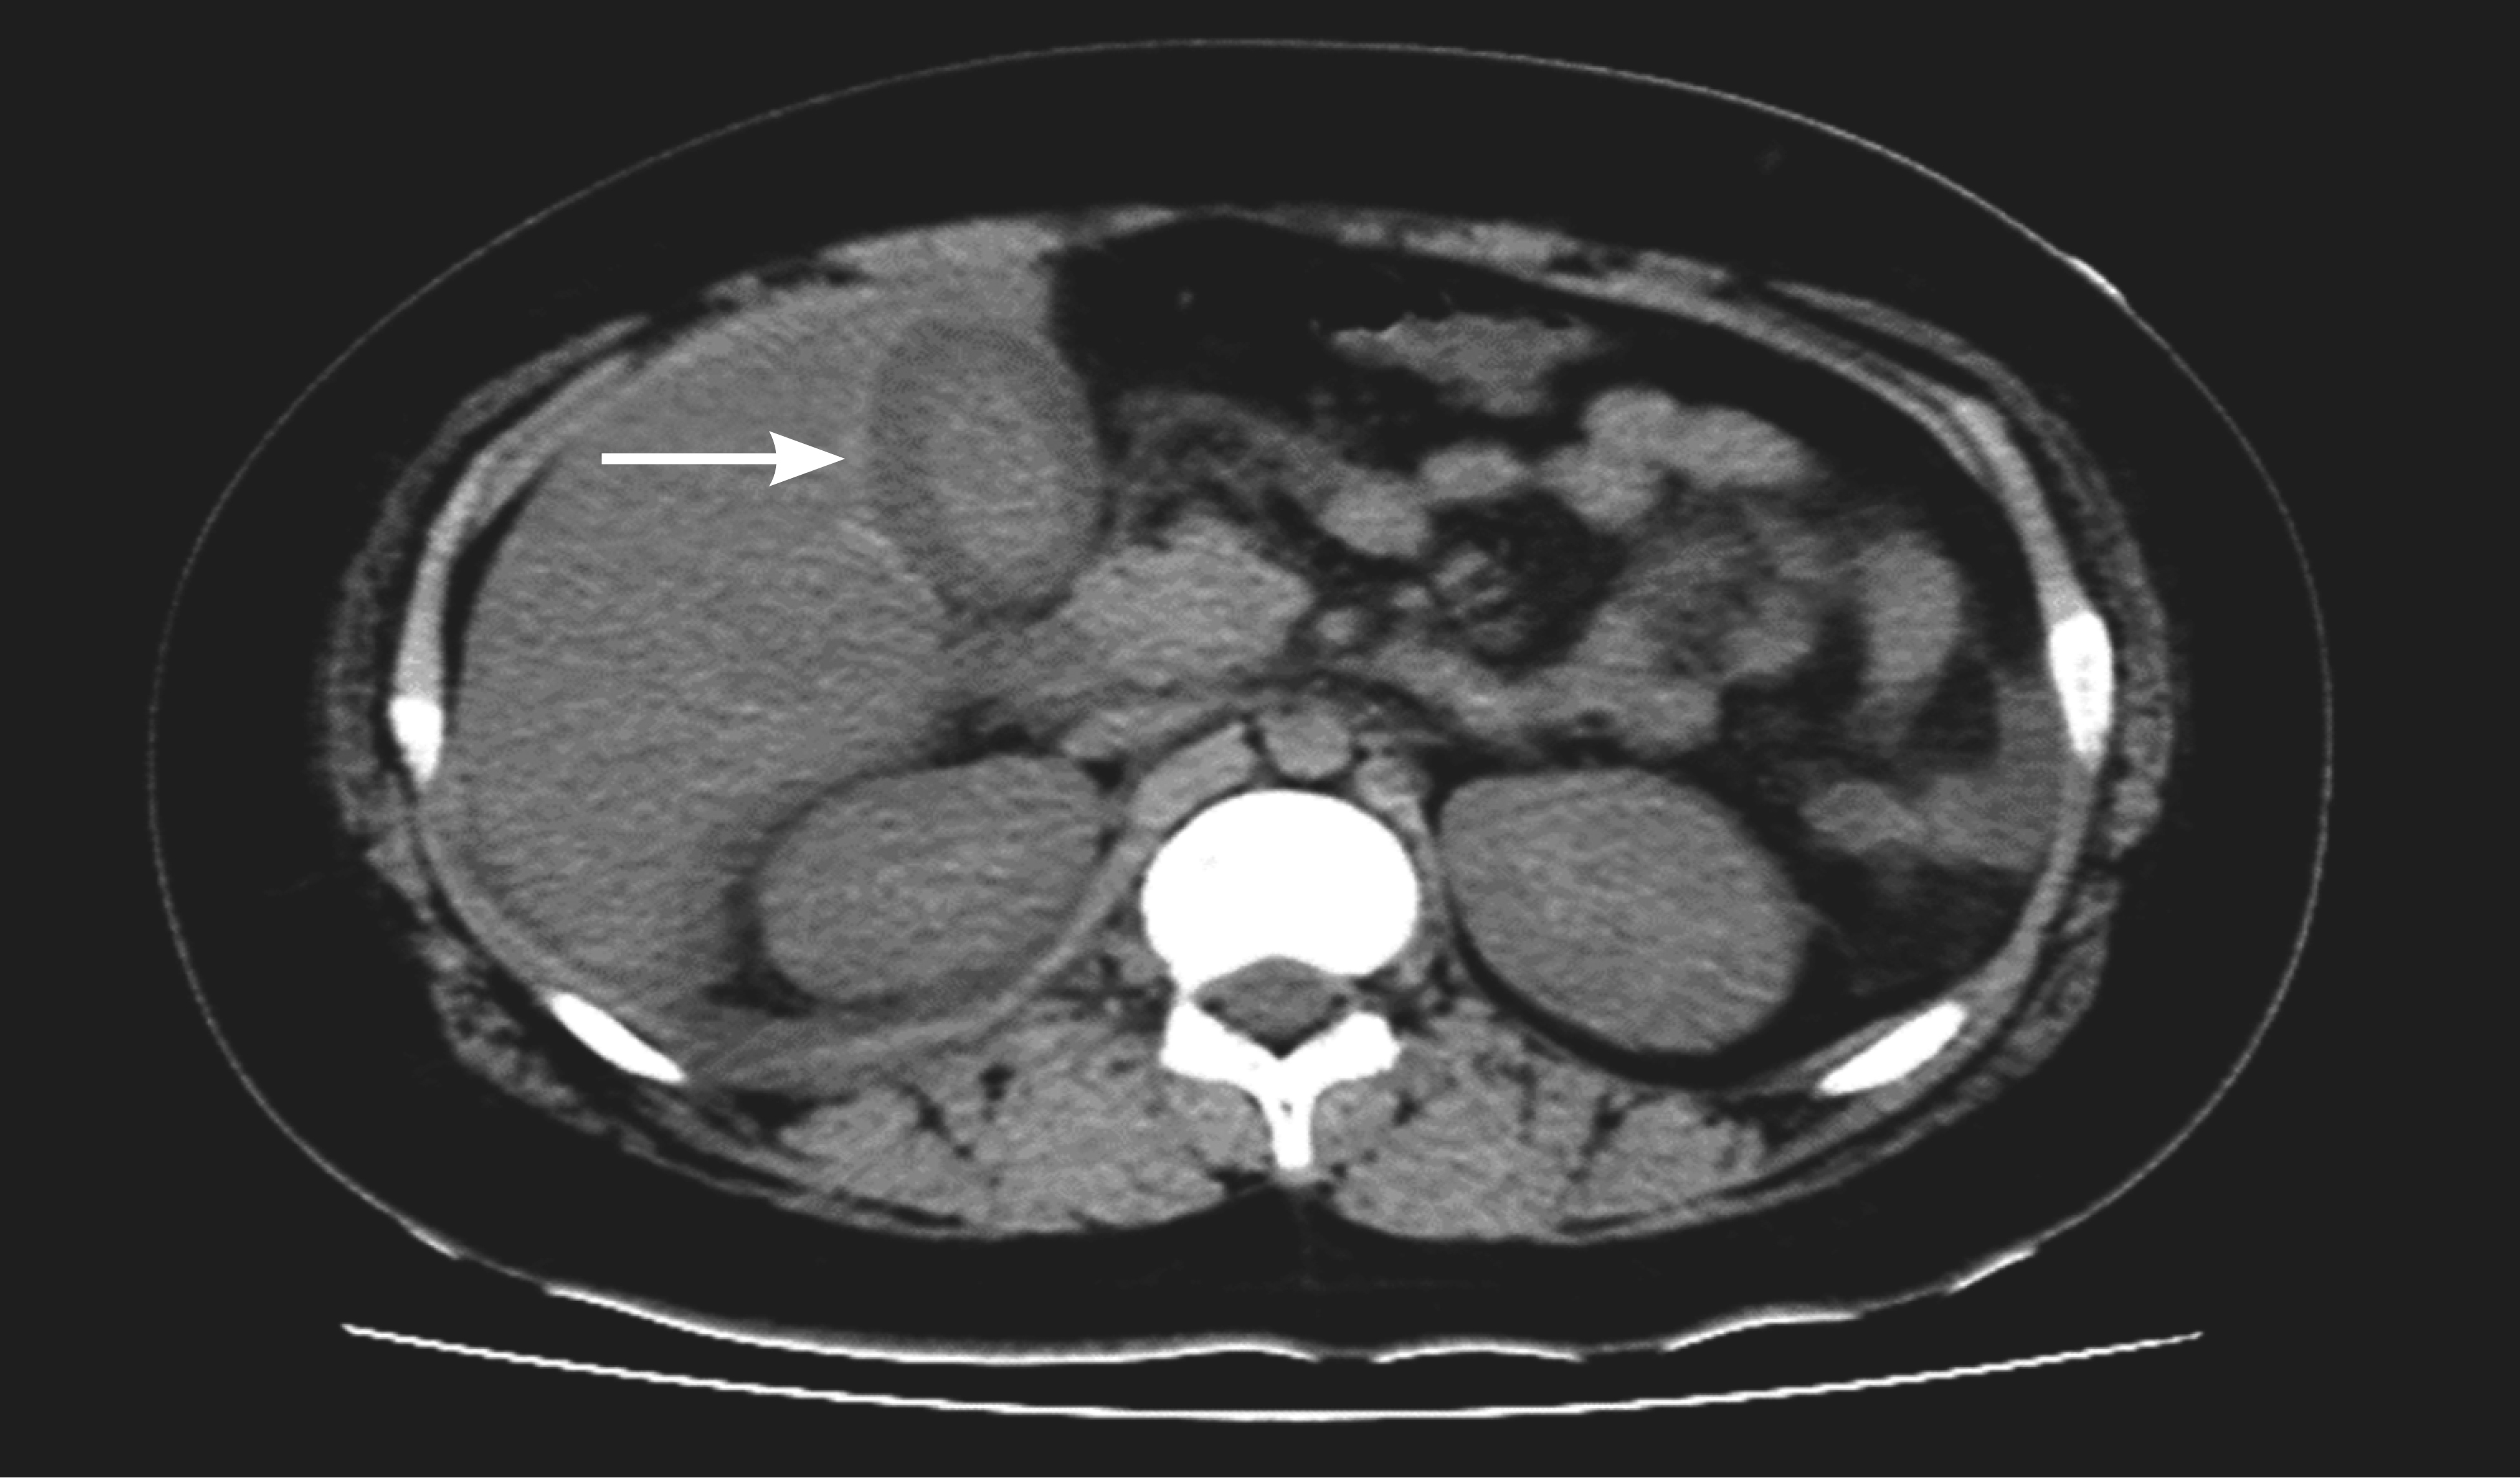

Figure 2